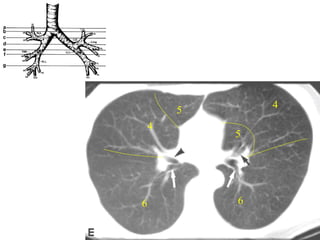

CAÂY PHEÁ QUAÛN VAØ PHAÂN THUØY PHOÅI

+CT cho chi tieát giaûi phaãu toát raát nhieàu so vôùi X

quang qui öôùc

+Phaân tích hình aûnh CT

-Caây pheá quaûn

-Phaân thuøy phoåi

-Raõnh maøng phoåi

Ngang möùc cung

ñoäng maïch chuû

3

2

1/2

1

6

Möùc Carina

Möùc ñoäng

maïch phoåi (T)

maïch phoåi (P)

5

4

Möùc nhó T

10

8

9

7/8

TOÙM LAÏI

• Ngang möùc carina: thaáy ñoäng maïch phoåi (T), thaáy

pheá quaûn (P) chia cho thuøy treân baét ñaàu thaáy

phaân thuøy 6 (P).

• Ngang möùc ñoäng maïch phoåi (P): thaáy pheá quaûn (T)

chiaheát thuøy treân xuaát hieän thuøy giöõa, thuøy

löôõi.

• Ngang möùc nhó (T): pheá quaûn (P) chia thuøy giöõa-

döôùi heát phaân thuøy 6 phaân thuøy 8,9,10.

• Ngang möùc 4 buoàng heát haï phaân thuøy 4 (T).